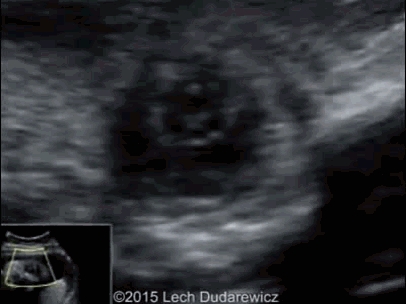

图 3 为以往某孕 15 周的先天性白内障;图 4 为本例孕妇 34 周先天性白内障及永存玻璃体动脉

图 5 为胎儿眼部超声所见:眼球过小,白内障,晶状体回声增强,其后方可见残存的玻璃体动脉;lens:白内障;hyaloid artery:玻璃体动脉;图 6 为正常胎儿眼球的对照图像,注意其晶状体回声与图 5 的差别